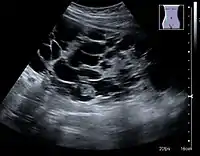

Figure 20. Staghorn calculi filling the entire collecting system and creating pronounced shadowing.[1]